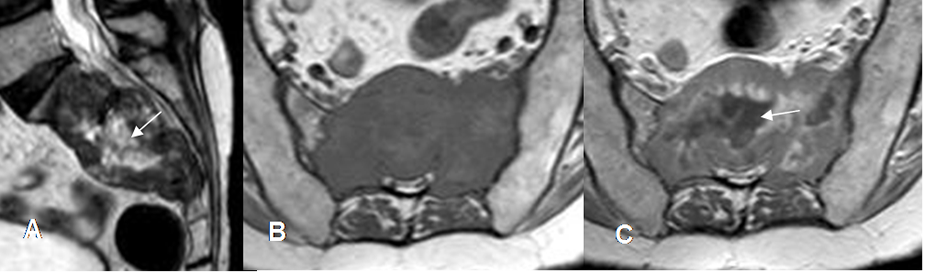

Fig 155. Metástasis mixtas.

A: TAC reconstrucción sagital en ventana de tejido, B: TAC reconstrucción sagital en ventana ósea y C: TAC axial. Múltiples lesiones líticas (Flechas delgadas) y blásticas (Flechas gruesas), por neoplasia de mama.

Fig 156. Metástasis mixtas.

A: RM sagital en T1, B: RM sagital en T2 y C: RM sagital en STIR. Igual paciente anterior. Alteración en la señal de L2 y L4, hipointensas en T1 y T2 e hiperintensas en STIR, por metástasis mixtas de neoplasia de mama.